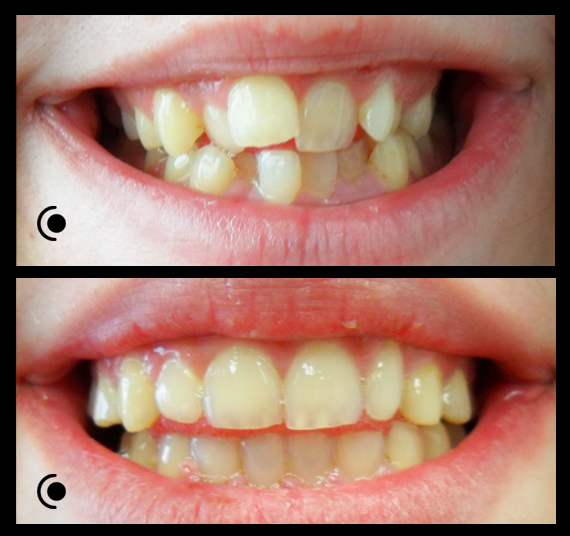

O našoj kvaliteti najbolje govore naši rezultati!

Centar za ortodonciju Petra Džapo